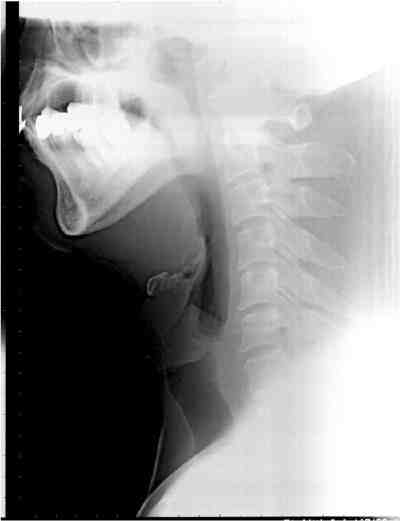

閉塞型睡眠時無呼吸症候群(OSAS)の閉塞部位はどこ?

また,原因となる疾患にはどんなものがあるの?

(OSASは気道の閉塞が原因ですから、気道を狭くする疾患が隠されています。) 睡眠時無呼吸症候群の診断はどうやってするの?